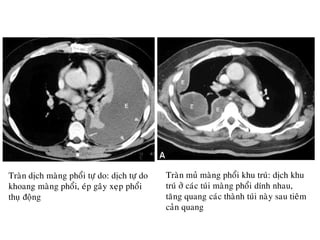

Traøn dòch maøng phoåi töï do: dòch töï do

khoang maøng phoåi, eùp gaây xeïp phoåi

thuï ñoäng

Traøn muû maøng phoåi khu truù: dòch khu

truù ôû caùc tuùi maøng phoåi dính nhau,

taêng quang caùc thaønh tuùi naøy sau tieâm

caûn quang